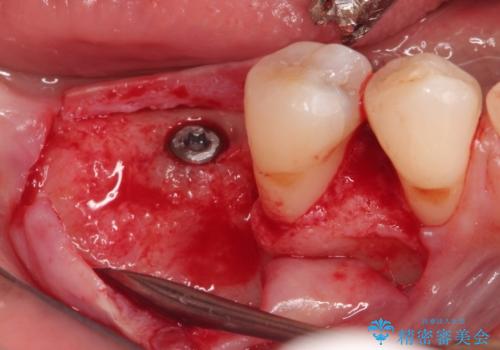

- 奥歯が破折していたため、抜歯を行ったあとインプラントを埋入して咬合回復を行っております。

インプラント埋入時に骨が足りない場合にはインプラント埋入時に骨増生を行います